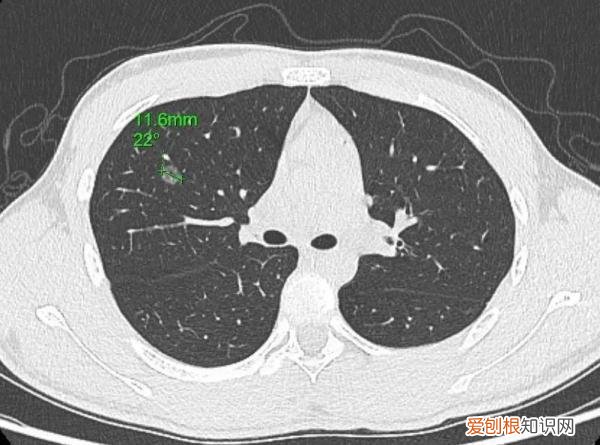

小亮的肺结节位于右上肺前段(1.16cm)

今年1月,父亲带着小亮和小亮外婆前往医院进一步就诊 。通过复查胸部CT,医生发现两人的肺结节都有不同程度增大,需尽早手术 。小亮和外婆当天就办了入院,并安排在同一天手术,好在两人手术都很成功 。